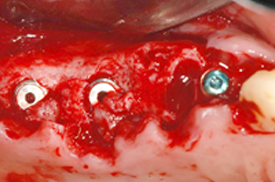

무절개 또는 최소절개

붓기와 출혈이 거의 없어 염증 및 감염의 위험이 적고

빠른 회복이 가능합니다.